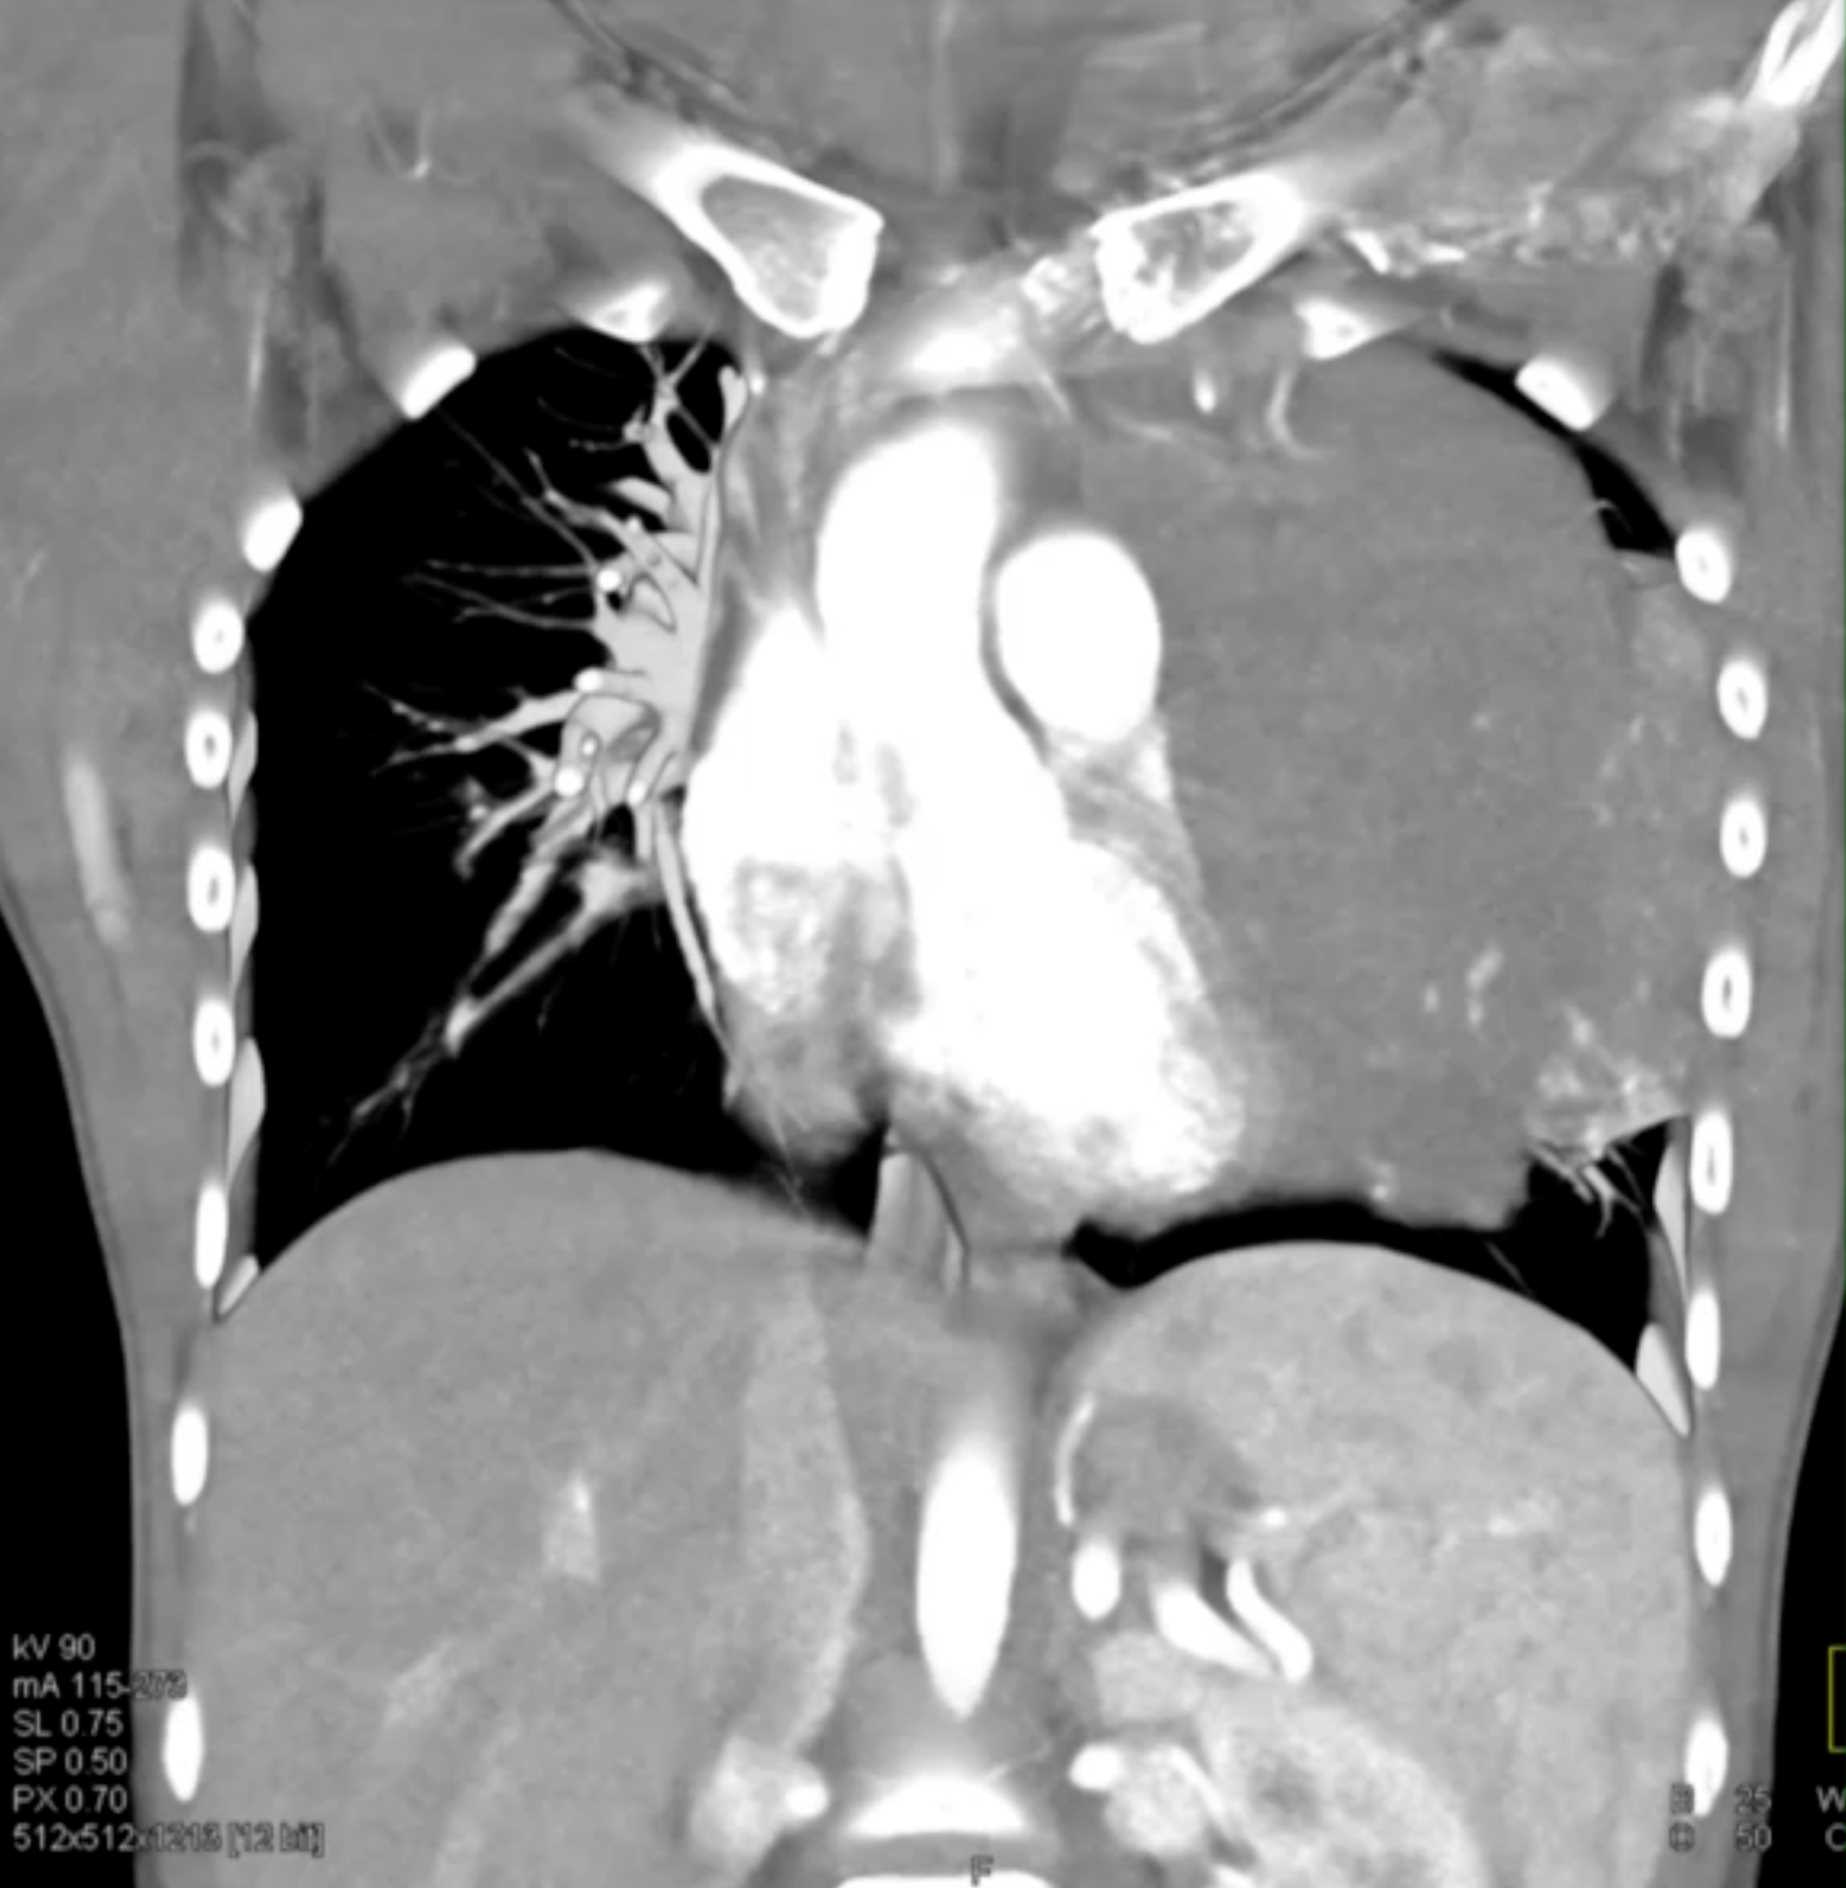

Subtle Adenocarcinoma Pancreas